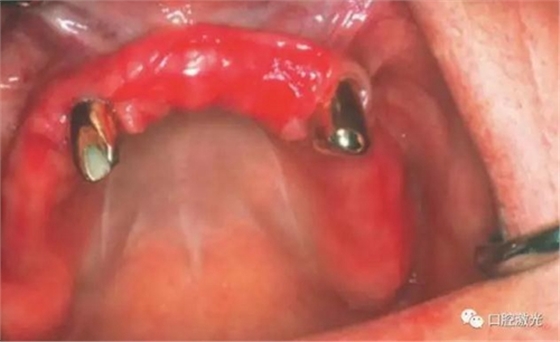

治療6個月后恢復情況

如今,種植體周圍炎的治療完成已經(jīng)過去了10多年,上顎義齒的狀況沒有再出現(xiàn)問題。種植體周圍組織基本健康。